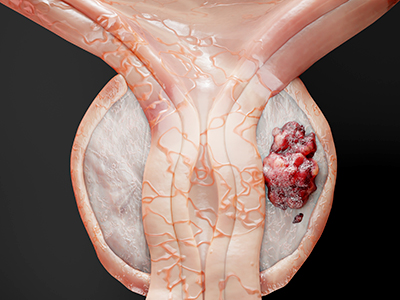

Prostate cancer is driven by androgens, which are male sex hormones, such as testosterone. The first-line treatment for prostate cancer is androgen deprivation therapy, designed to block androgen production in the body.

Approximately 30,400 Canadians are diagnosed with prostate cancer each year, with the vast majority of patients responding well to front-line therapies early in the disease progression. However, with time, most prostate cancers stop responding to androgen deprivation therapy and become treatment resistant.